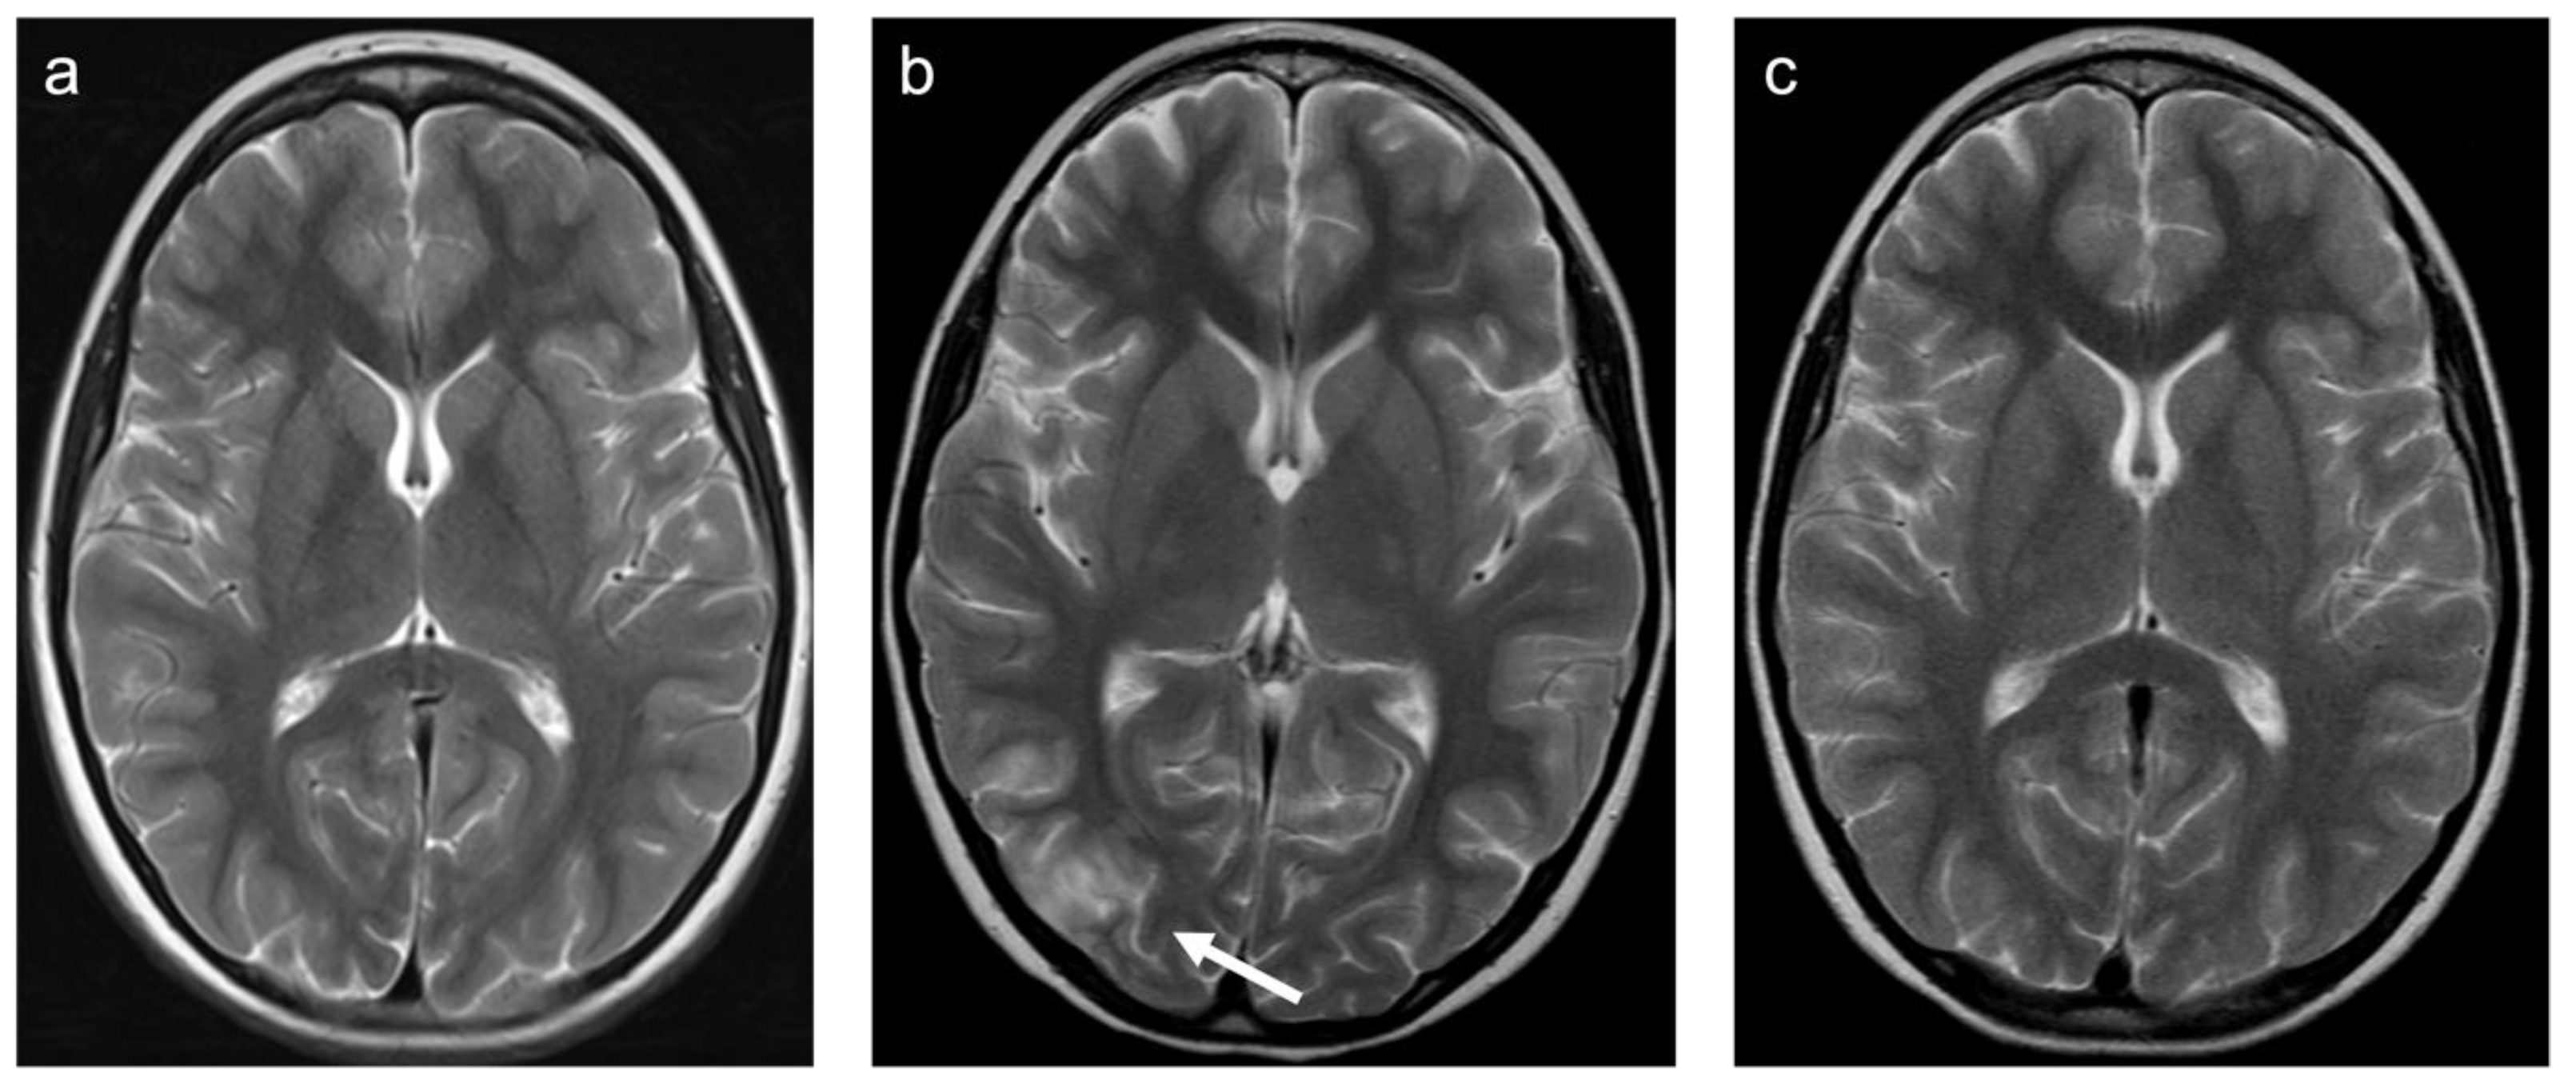

Group 8 consisted of 15 patients. Six patients were diagnosed with a posterior reversible encephalopathy syndrome (PRES). Eight were diagnosed with a toxic leukoencephalopathy, predominantly related to high-dose, multidrug chemotherapy. Two cases were related to cranial radiation and immunosuppressive drugs (Ciclosporin A), respectively. A representative case is shown in Figure 8. A total of 60% patients were female and the mean age was 4.6 years (min 1.7 years; max 18.4 years). In total, 93% of patients were examined with contrast-enhanced MRI. Of those examinations, 29% showed enhancing lesions. WMSAs in this group of patients were localized supratentorial only. A total of 87% of patients had multifocal WMSAs.

Figure 8. Representative case “Toxic white matter injuries”: L-asparaginase treatment. T2W (ac) sequences. ten-year-old boy with induction of L-asparaginase treatment of acute lymphoblastic lymphoblastic leukemia. MRI prior to treatment (a), shortly after induction of treatment showing vasogenic edema within the right (white arrow) and, of lesser extent, left occipital region ((b); clinical presentation: epileptic seizure) with patchy enhancement in a leptomeningeal pattern (not shown) and restitution after treatment stop (c).